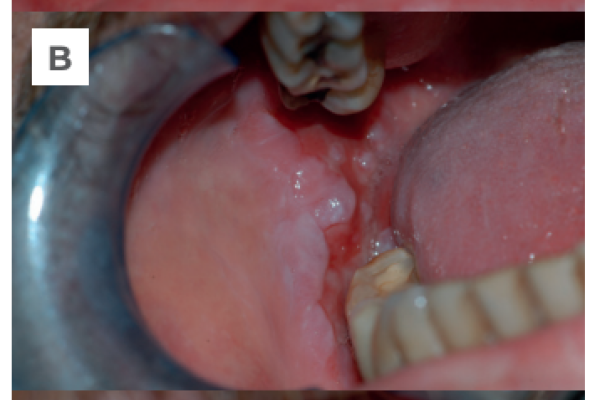

Pénfigo Vulgar mucoso: a propósito de un caso. Revisión de la literatura